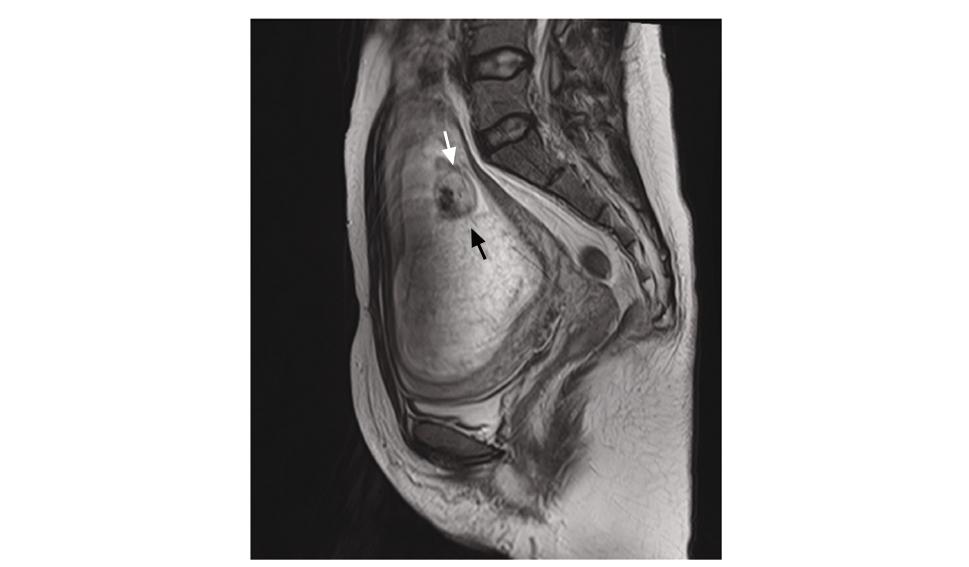

孕14周时盆腔MRI可见胎儿影(白色箭头)及葡萄胎组织异常信号(黑色箭头)